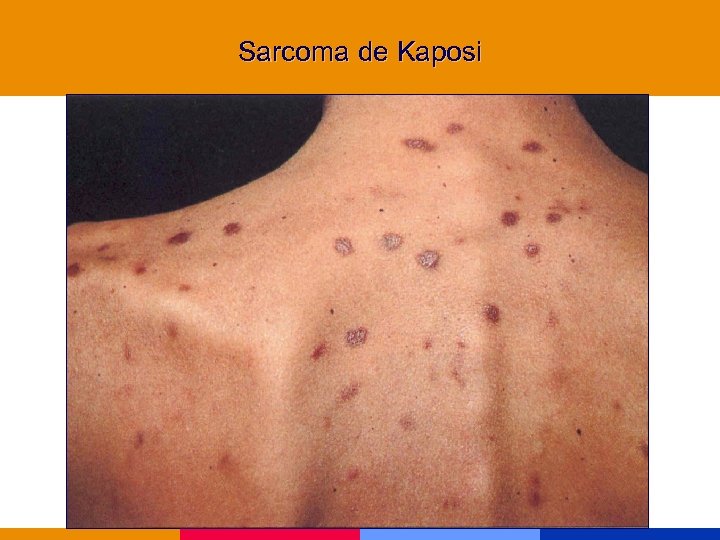

Categoría C (Enfermedades marcadoras) § Cáncer de cuello uterino, invasivo § Sarcoma de Kaposi § Linofoma no Hodking, primario de SNC

Categoría C (Enfermedades marcadoras) § Cáncer de cuello uterino, invasivo § Sarcoma de Kaposi § Linofoma no Hodking, primario de SNC

Neoplasias marcadoras § Cáncer de cuello uterino, invasivo § Sarcoma de Kaposi § Linofoma no Hodking, primario de SNC Incremento de otras neoplasias: pulmón, seminoma, melanoma, otras

Neoplasias marcadoras § Cáncer de cuello uterino, invasivo § Sarcoma de Kaposi § Linofoma no Hodking, primario de SNC Incremento de otras neoplasias: pulmón, seminoma, melanoma, otras

Sarcoma de Kaposi

Sarcoma de Kaposi

Sarcoma de Kaposi

Sarcoma de Kaposi

Sarcoma de Kaposi

Sarcoma de Kaposi

Sarcoma de Kaposi

Sarcoma de Kaposi